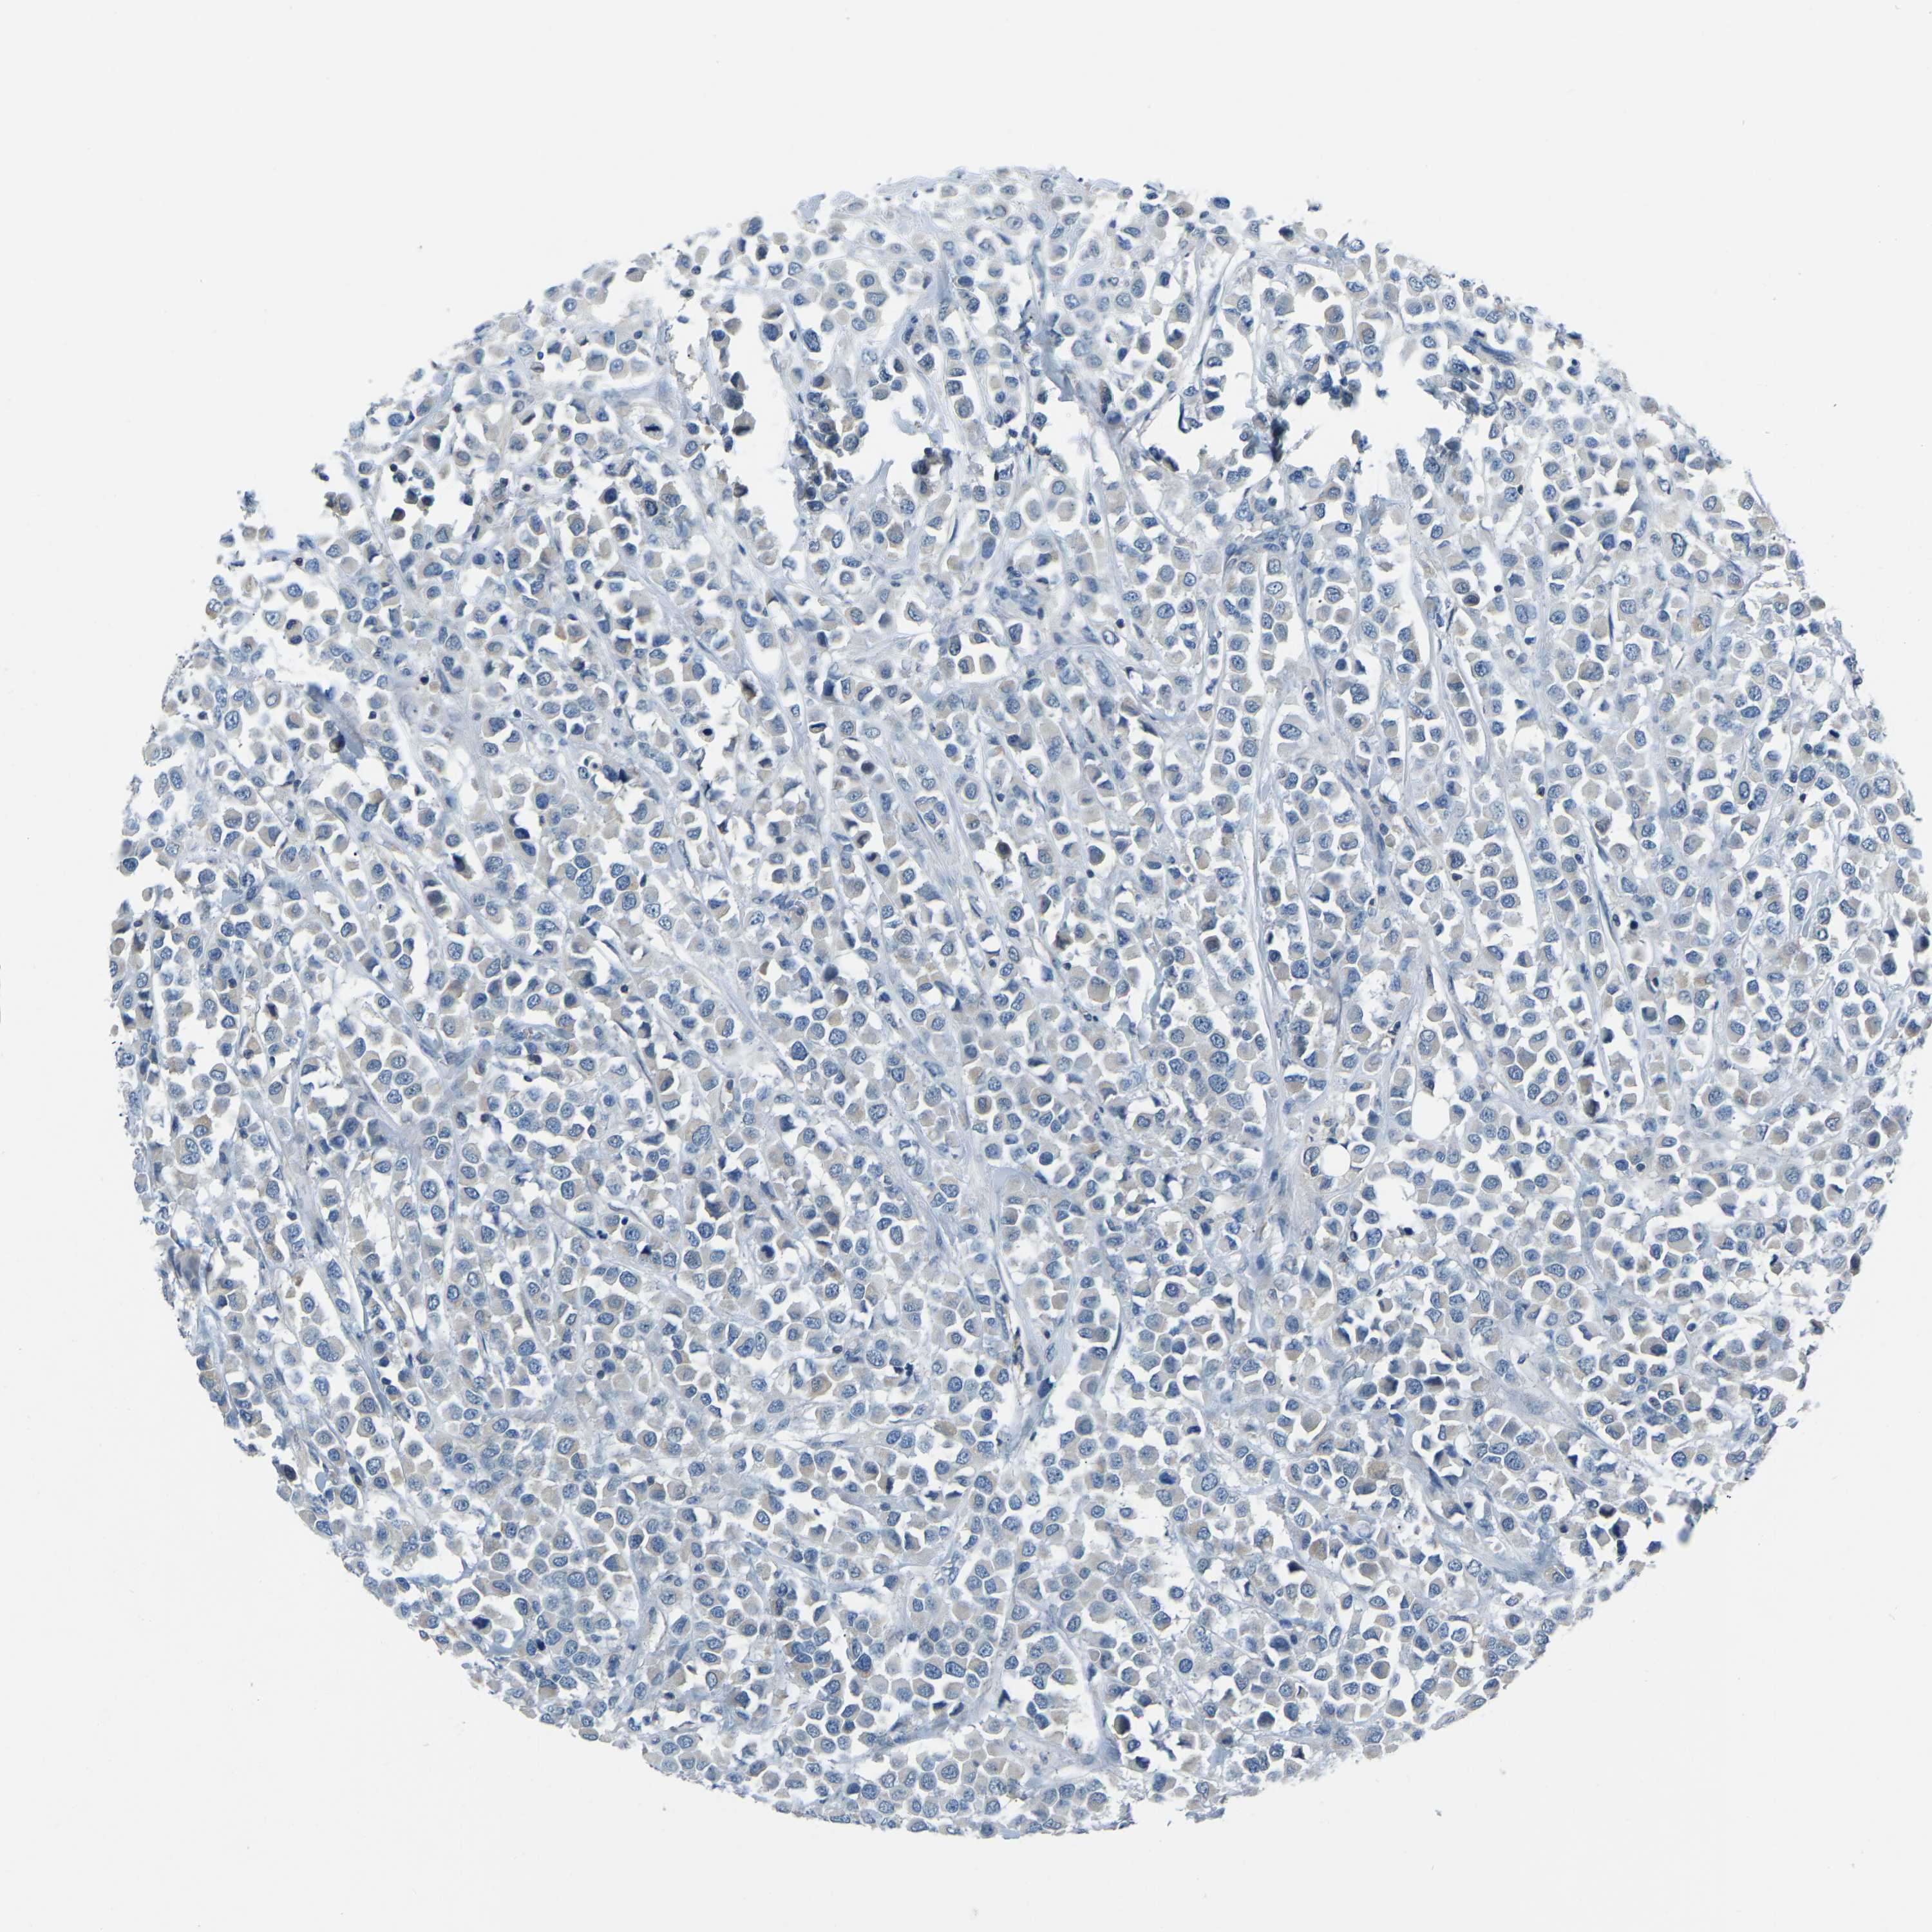

BRCA TCGA BRCA VALIDATION PROTEIN EXPRESSION